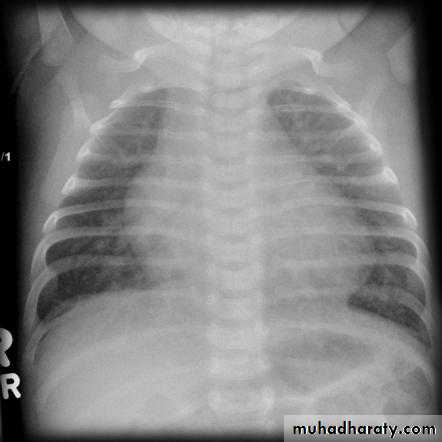

• CXR:

• cardiomegal• Rt atrial enlargement

• prominent PA

• increased pulmonary vascularity.